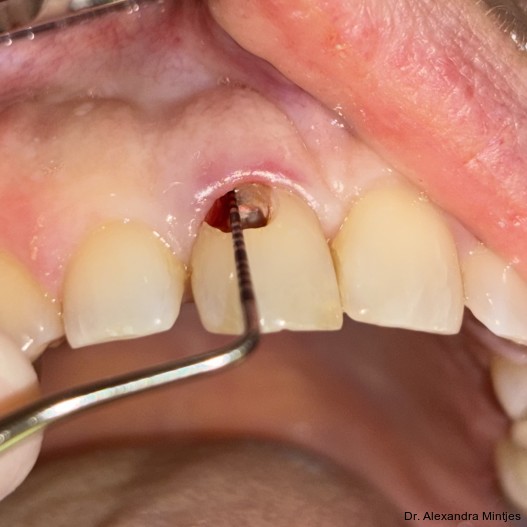

Bei der Erstvorstellung zeigte die vorhandene Füllung einen deutlichen Randspalt, war verfärbt und nach apikal hin insuffizient. Klinisch präsentierte sich ein dicker gingivaler Phänotyp mit ­harmonischer Weichgewebsbalance, jedoch bestand distal eine lokalisierte, entzündliche Zahnfleischtasche (Abb. 1). Es war zu vermuten, dass das nekrotische bzw. resorptive Hartgewebe nicht vollständig entfernt worden war. Auf dem DVT wurde das Ausmaß des Defekts deutlich. Zu­dem ließ sich eine deutliche apikale Aufhel­lung nachweisen, die Patientin war jedoch beschwerdefrei (Abb. 2).

Die Behandlung erfolgte in mehreren präzisen aufeinander abgestimmten Schritten. Zunächst wurde die alte Kompositfüllung vollständig und atraumatisch entfernt, ohne eine Blutung der Schleimhaut zu provozieren. Nur durch das minimalinvasive und vorsichtige Vorgehen bei der Entfernung der insuffizienten Kompositfüllung konnte die Blutungsfreiheit erreicht und somit eine solide Grundlage für die folgenden Behandlungsschritte gewährleistet werden. Anschließend wurde die weiche Zahnhartsubstanz mithilfe eines Rosenbohrers sorgfältig exkaviert (Abb. 3). Überschüssige Guttapercha wurde ebenfalls abgetragen, um eine saubere und stabile Basis zu schaffen.